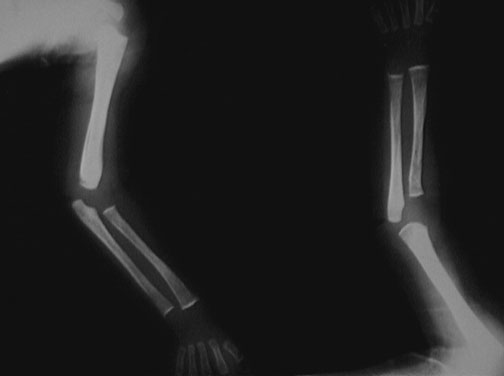

The long bones of the arms reveal increased lucency with epiphyseal widening characteristic for scurvy.